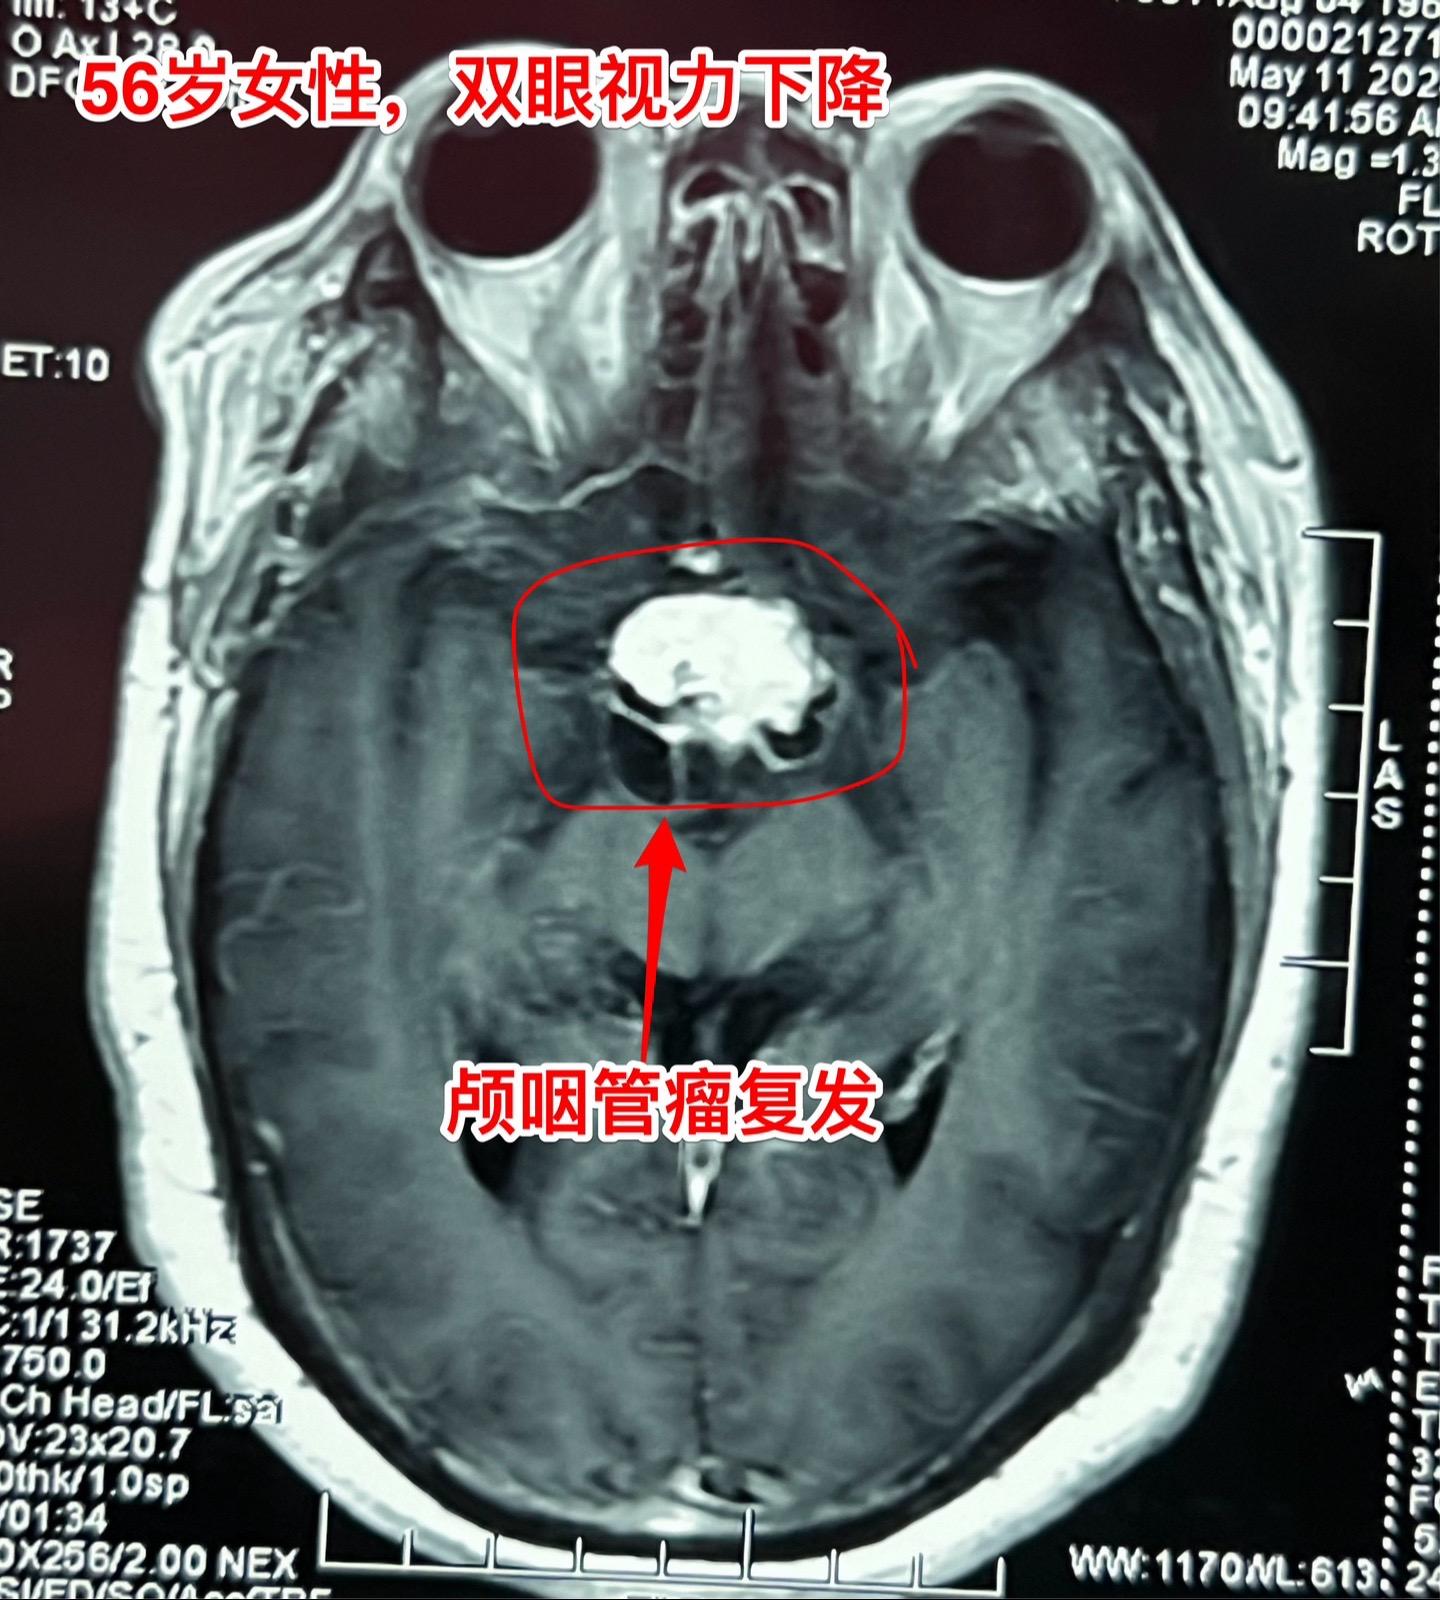

5月17日两例颅咽管瘤手术。第一例患者56岁,双眼视力都很差了,之前做过两次开颅手术,为乳头型颅咽管瘤复发。 第二例患者,24岁男性,因视力下降发现颅咽管瘤,也是乳头型颅咽管瘤。 两例患者手术入路不同,效果都满意,颅咽管瘤均得到完全切除。希望肿瘤不复发。